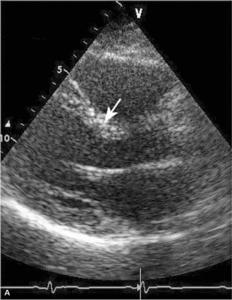

Głównym mechanizmem patogenetycznym twardziny układowej jest zwiększona produkcja aminopropeptydu kolagenu typu III, w następstwie czego dochodzi do włóknienia tkanek (ryc. 1). Zwiększenie sztywności naczyń koreluje z zaawansowaniem choroby [3-5] i może prowadzić do ciężkiego powikłania, jakim jest tętnicze nadciśnienie płucne (ryc. 2, 3) [6].